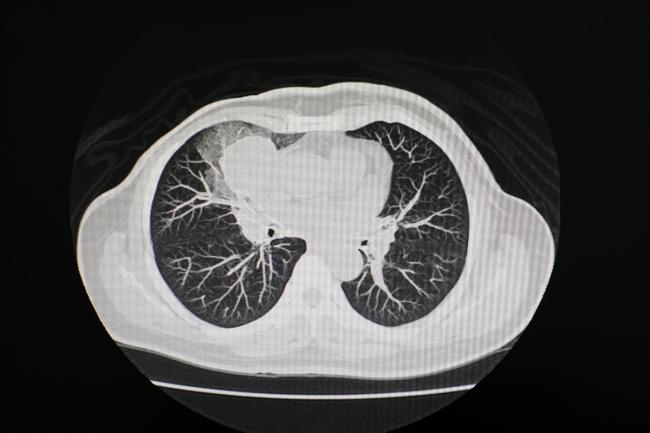

A research team funded by the National Institutes of Health (NIH) has developed a versatile machine learning model that could one day greatly expand what medical scans can tell us about disease. Scientists used their tool, named Merlin, to assess 3D abdominal computed tomography (CT) scans, accomplishing tasks as simple as identifying anatomical features to as complex as predicting disease onset years in advance. Despite being developed as a general-purpose CT model, Merlin surpassed a gauntlet of similar automated tools in tasks they were specifically built to handle.

The researchers ramped up the difficulty further by challenging Merlin to interpret CT scans of the chest, a body part completely absent from its CT study material. Merlin’s unique ability to identify generalizable features of disease allowed it to perform as well as or better than models trained exclusively on chest scans.